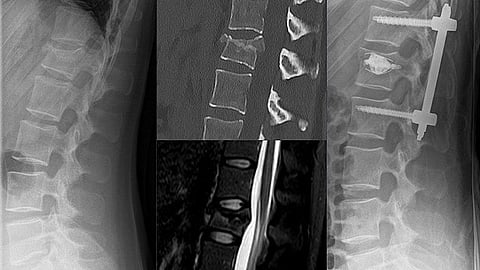

Surgeons at KIMS Hospital, Kondapur, performed vertebral body stenting on a 65-year-old woman, who had suffered a fracture after a fall.

Using the latest surgical technique, the surgeons planted the stent in the spine to stabilise the fracture. This is claimed to be the first such procedure in Hyderabad.

Vertebral body stenting is a minimally invasive technique where a metal stent is used to stabilise fractures, just like a cardiac stent.

The patient had not recognised the fracture that was caused due to the fall. After a scan at KIMS, renowned spinal surgeon Dr Krishna Chaitanya recognised a fracture in her L2 vertebral bone and suggested vertebral body stenting to ensure best recovery.

About the benefits of this procedure, Chaitanya said: "The entire procedure is done in 20 minutes with no blood loss. In previous procedures, the operation would last for 3-4 hours where screws are fixed to reduce the fracture and it also causes heavy blood loss and many months of recovery. Whereas in Vertebral Body Stenting, a small needle goes inside the spine through which a stent is sent and it would spread across the bone and fix it in its original position. For example, when a person has a spinal fracture, the bone height would reduce by 0.5 mm-1 cm. The stent would ensure the bone reaches the same height as before. There is also no pain involved in this procedure and the patient can easily walk within a few hours post operation."